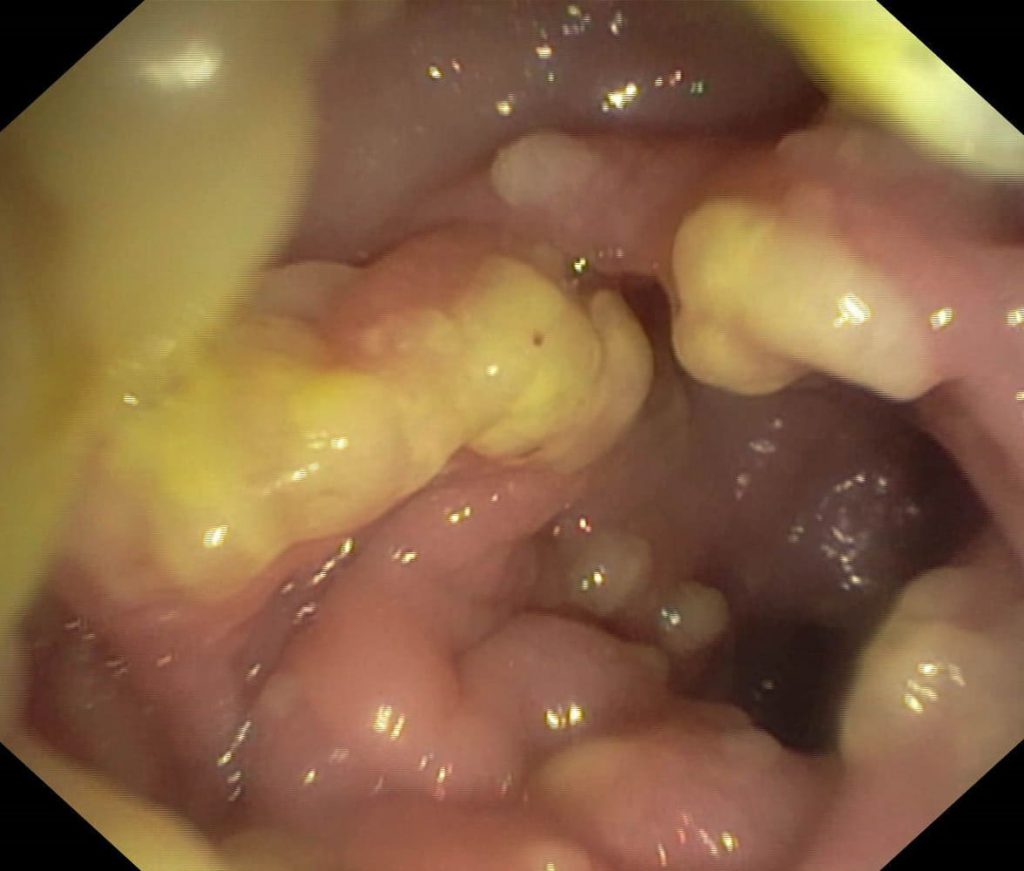

سندرم لینچ یا کنسرکولون غیرپولیپی ارثی (HNPCC) بیماری فامیلی است که در اثر جهش اتوزومال غالب ایجاد میشود. با رخداد این جهش تعدادی آدنوم کوچک در کولون ایجاد شده و این آدنومها میتوانند به سمت سرطانی شدن پیش بروند. همچنین این افراد در ریسک بالای ابتلا به سرطانهای اندومتر، معده و تخمدان هستند.